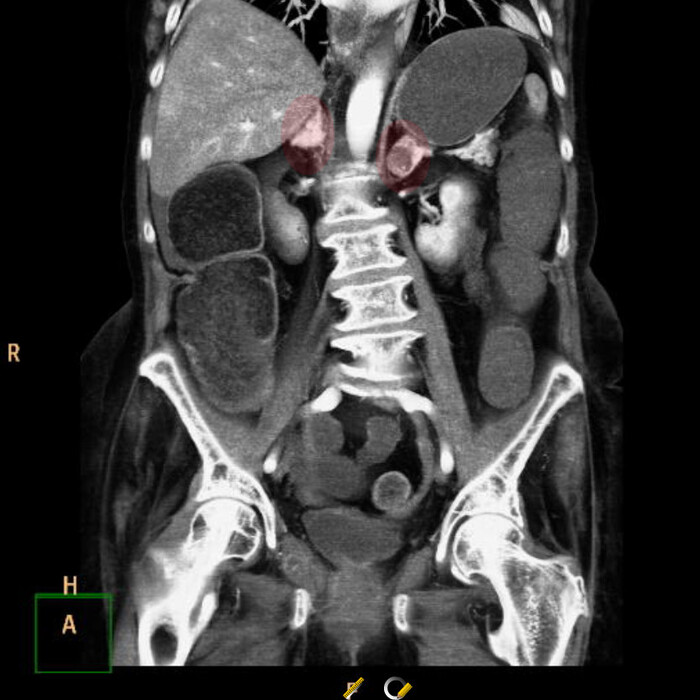

В лёгочном окне - очаги консолидации ("уплотнения" лёгочной ткани) в постеробазальных (задне-нижних) отделах правого лёгкого (на ренгенснимках и КТ, а также МРТ та часть, что на мониторе расположена слева - всегда правая сторона пациента). На последнем снимке серии ниже (сагиттальная или боковая реконтрукция) были непонятные артефакты, как от металла:):

Переключаемся на "костное" окно (позволяет луче оценить кости и прочие плотные структуры), где реально видим "металлический" предмет в просвете правого нижнедолевого бронха:

сагиттальная, аксиальная и корональная реконструкция